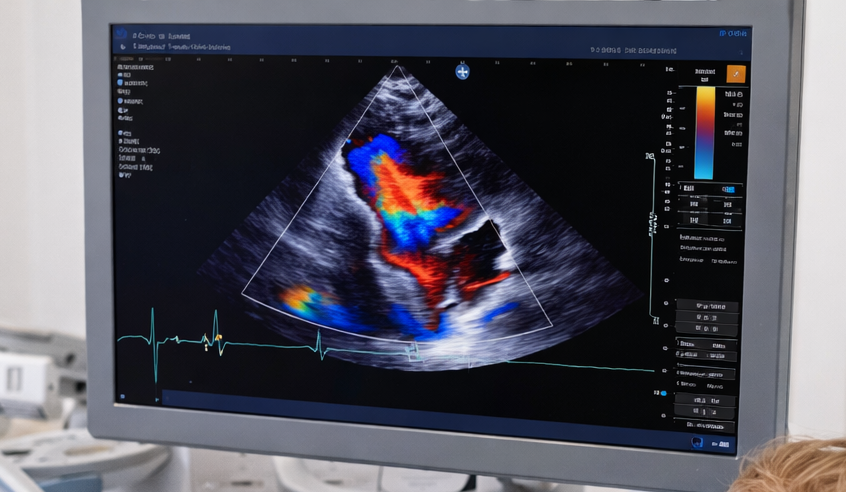

Alcuni video di patologie cardiache

Nel sito del centro cardiologico infantile del Dott. Enrico Rosati troverai alcuni video riguardanti alcuni casi di cardiopatie fetali diagnosticati presso lo studio medico di Brindisi. I video riguardano l'atresia polmonare, l'anomalia di Ebstein, la coartazione aortica, il TGA fetale e il canale atrioventricolare. Non esitare a contattare la segreteria per richiedere informazioni o fissare un appuntamento per il tuo bambino.